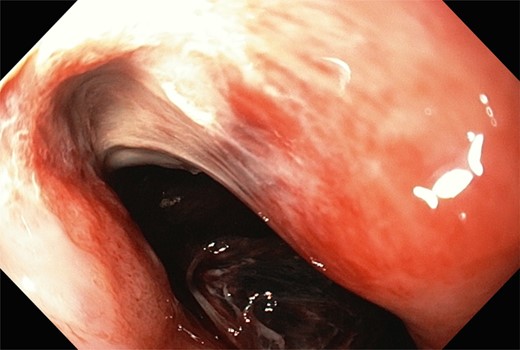

Gastroscopy the following day showed a fundal gastric ulcer and the MWT, which was now larger and deeper (Fig. 2). On Day 10, the patient underwent surgery. A midline laparotomy incision was performed, followed by extensive adhesiolysis. After the anterior wall of the stomach was exposed from the GEJ to pylorus, a longitudinal gastrotomy was created over the fundus. There was a deep MWT at GEJ extending along the greater curve of the stomach, which was bleeding actively. The MWT was oversewn with interrupted 3/0 PDS sutures and hemostasis achieved. A second, larger fundal ulcer, presumably from pressure necrosis of SB tube, was also noted. This ulcer occupied most of the fundus of stomach, which was excluded from the gastric cavity, by the closure of fundus with interrupted 3/0 PDS (Fig. 3). Postoperatively, oral fluids were commenced on Day 12. On Day 15, a Gastrografin swallow study was normal, and oral intake was encouraged. The patient recovered without complications and returned to the rehabilitation facility.

During the last gastroscopy, a fundal gastric ulcer and a larger and deeper Mallory–Weiss tear were noted.